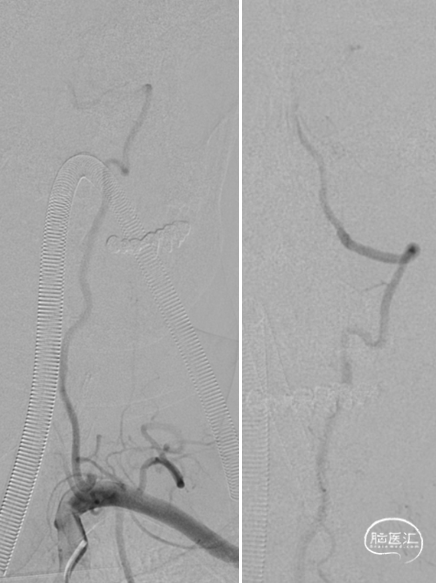

经桡入路造影

造影示:右侧优势椎,经右侧椎动脉导弯造影,双侧胚胎型大脑后动脉。

术前DSA:双侧后交通动脉开放。

R-VA

L-SUB-VA